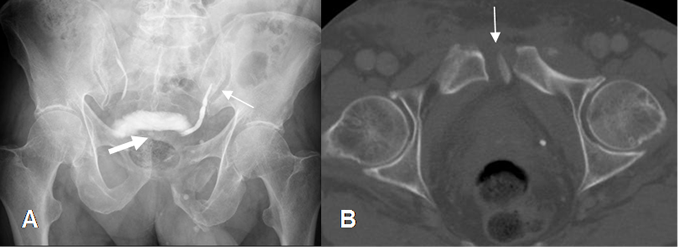

Fig 38. Trauma de pelvis.

A: Rx AP. Diastasis de la sínfisis púbica y sacroiliaca izquierda. (Flecha delgada). Hay luxofractura del pubis izquierdo, con hematoma en la pelvis, que comprime la parte posterior de la vejiga. (Flecha gruesa).

B: TAC corte axial. Luxofractura del pubis izquierdo.